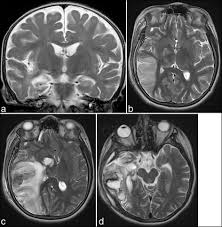

Encephalitis in the immunocompromised host. Its symptoms are fever, confusion, coma, and seizures. Clinical, magnetic resonance imaging, and electroencephalographic findings in paraneoplastic limbic encephalitis. Alpha coma in japanese encephalitis. In children older than 3 months and in adults brain biopsy: Pregnancy the most common cause of encephalitis in newborns is vaginal delivery from a mother who is infected with herpes simplex virus 2 (hsv 2). Mri is the imaging of choice in suspected cases of viral encephalitis, although ct scanning may be used where mri facilities are not available. Herpes simplex encephalitis occurs as 2 distinct entities: Brain mri—increased t2 signal intensity in frontotemporal region → viral (hsv) encephalitis. • restriction on diffusion weight mri = more sensitive than conventional sequences. Hsv pcr and other infectious studies from the serum and csf were negative. Initial brain ct scanning was unremarkable but a subsequent mri scan showed features consistent with herpes simplex virus encephalitis. Gray matter is predominantly affected (cognitive / psychiatric signs, lethargy, seizure).

Herpes Simplex Virus Encephalitis Neurology Learning Network from www.neurologylearningnetwork.com Brain changes in herpes simplex virus (hsv). Brain mri is shown in fig. Brain mri—increased t2 signal intensity in frontotemporal region → viral (hsv) encephalitis. A case of granulomatous hsv encephalitis: Dhawan a, kecskes z, jyoti r, kent al. Alpha coma in japanese encephalitis. Contrast enhancement is uncommon during the first week of the disease. Encephalitis caused by hsv type 1 is rare but can result in significant brain damage or death.

Brain changes in herpes simplex virus (hsv). Encephalitis in the immunocompromised host. Hsv pcr and other infectious studies from the serum and csf were negative. Severe infection, particularly untreated herpes simplex virus (hsv) encephalitis, can cause brain hemorrhagic necrosis. Pregnancy the most common cause of encephalitis in newborns is vaginal delivery from a mother who is infected with herpes simplex virus 2 (hsv 2). Alpha coma in japanese encephalitis. Contrast enhancement is uncommon during the first week of the disease. Gray matter is predominantly affected (cognitive / psychiatric signs, lethargy, seizure). Diagnostic uncertainty and empirical management in pcr negative encephalitis. The study analysed serially acquired magnetic resonance images (mri), of patients with acute hsv encephalitis who had neuroimaging repeated within four weeks of the first scan. In children older than 3 months and in adults brain biopsy: • restriction on diffusion weight mri = more sensitive than conventional sequences. Mri is the imaging of choice in suspected cases of viral encephalitis, although ct scanning may be used where mri facilities are not available.

Hsv Encephalitis Herpes Simplex Encephalitis Type 1 Immunology Microbiology Flashcards Draw It To Know It from d1j63owfs0b5j3.cloudfront.net It is a severe condition brain mri may show limbic encephalitis (55) or diffuse t2 and dwi hyperintensities in the white matter, associated with restricted diffusion (54). The laboratory diagnosis of autoimmune encephalitis. Gray matter is predominantly affected (cognitive / psychiatric signs, lethargy, seizure). There is no particular age, sex, or seasonal predilection. The patient had initially improved after medical treatment. Pregnancy the most common cause of encephalitis in newborns is vaginal delivery from a mother who is infected with herpes simplex virus 2 (hsv 2). Herpes simplex encephalitis occurs as 2 distinct entities: Diagnostic uncertainty and empirical management in pcr negative encephalitis.

The patient had initially improved after medical treatment. • occurs despite blood brain barrier with tight junctions. Mri is the imaging of choice in suspected cases of viral encephalitis, although ct scanning may be used where mri facilities are not available. It is a severe condition brain mri may show limbic encephalitis (55) or diffuse t2 and dwi hyperintensities in the white matter, associated with restricted diffusion (54). Herpes simplex virus (hsv) encephalitis hsv encephalitis (hsve) is the most common cause of infectious encephalitis (1); Gray matter is predominantly affected (cognitive / psychiatric signs, lethargy, seizure). The study analysed serially acquired magnetic resonance images (mri), of patients with acute hsv encephalitis who had neuroimaging repeated within four weeks of the first scan. Acute hsv encephalitis who had neuroimaging repeated within four weeks of the first scan. There is no particular age, sex, or seasonal predilection. Encephalitis caused by hsv type 1 is rare but can result in significant brain damage or death. Pregnancy the most common cause of encephalitis in newborns is vaginal delivery from a mother who is infected with herpes simplex virus 2 (hsv 2). A case of granulomatous hsv encephalitis: Initial brain ct scanning was unremarkable but a subsequent mri scan showed features consistent with herpes simplex virus encephalitis.